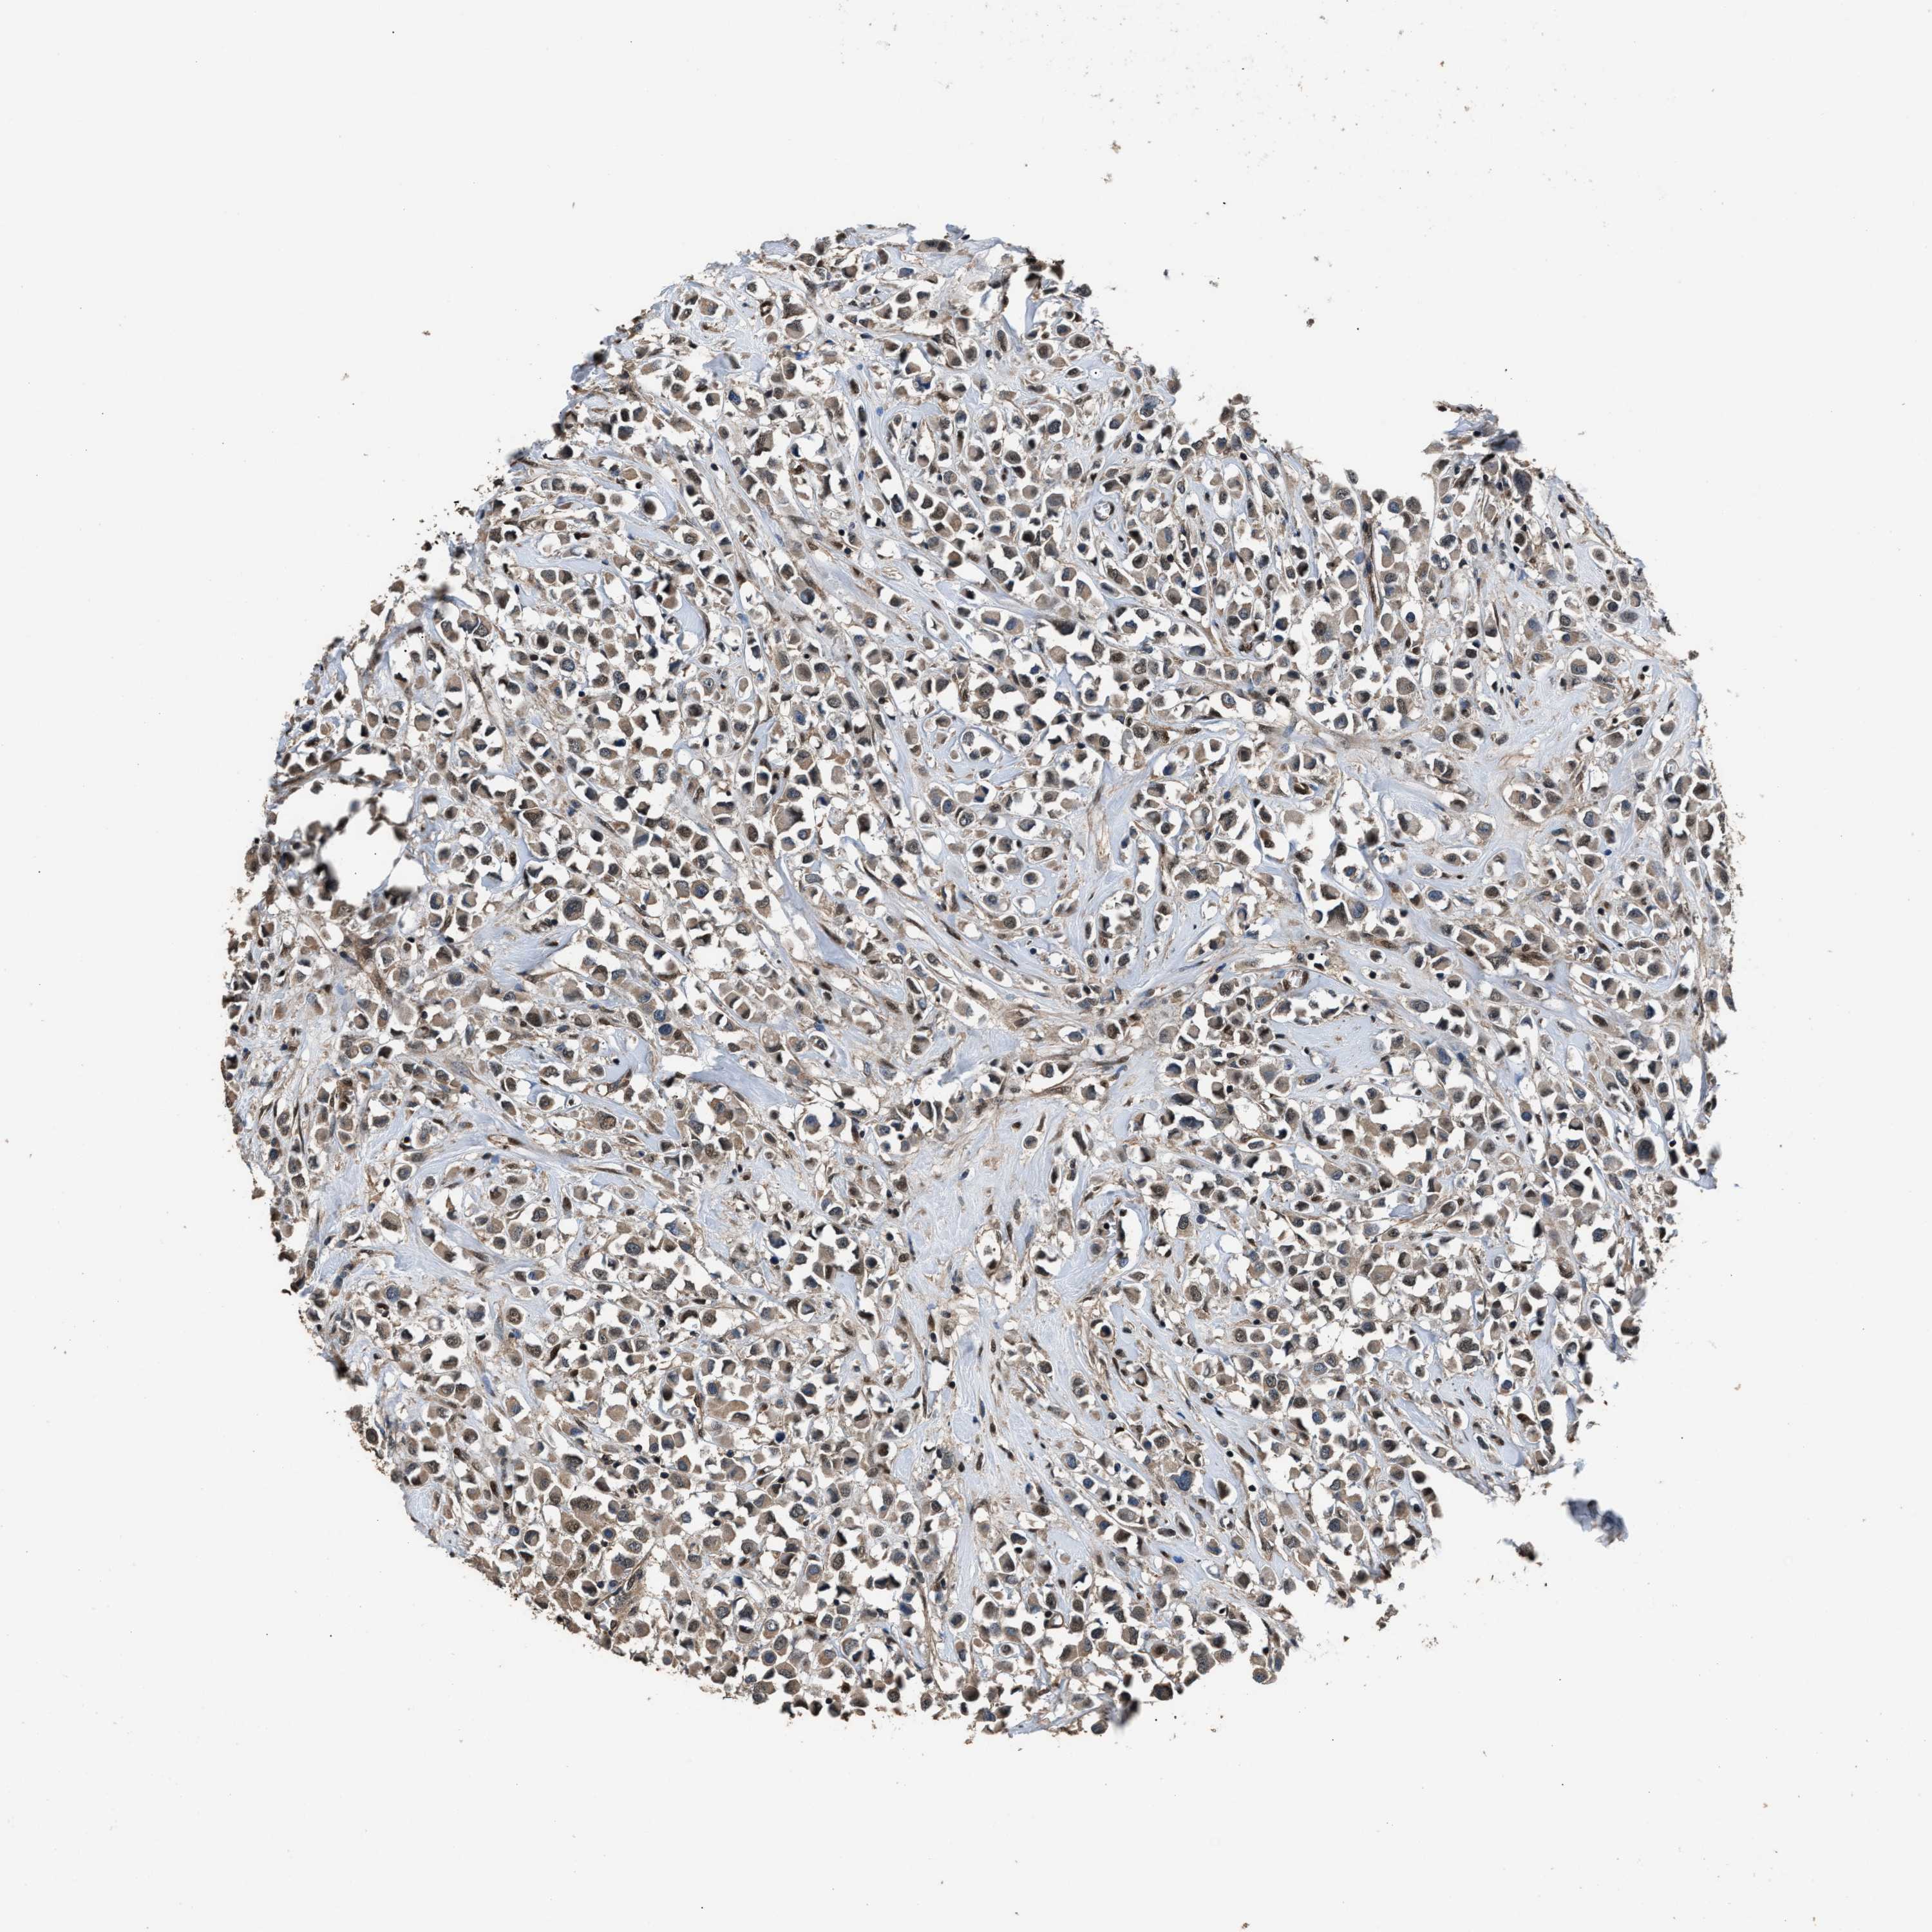

CANCER BREAST CANCER Show tissue menu

BRCA TCGA BRCA VALIDATION PROTEIN EXPRESSION